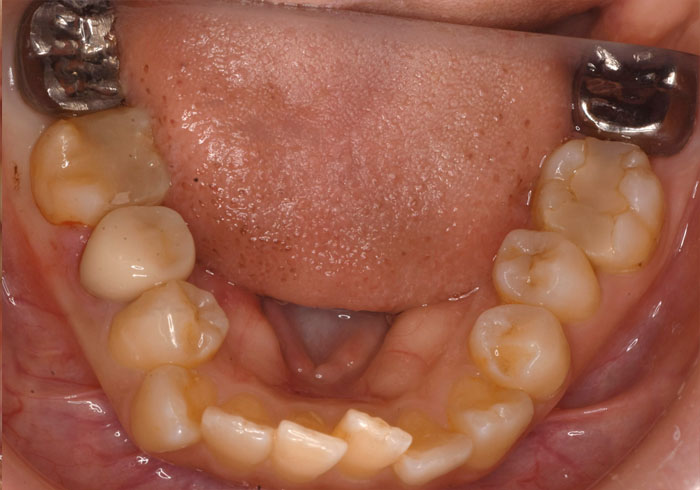

治療前

マウスピース矯正 マウスピース矯正 マウスピース矯正